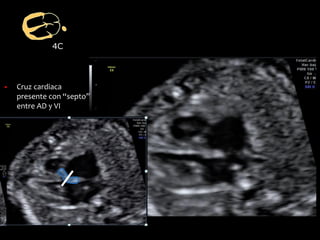

4C

▪ Cruz cardiaca

presente con “septo”

entre AD y VI